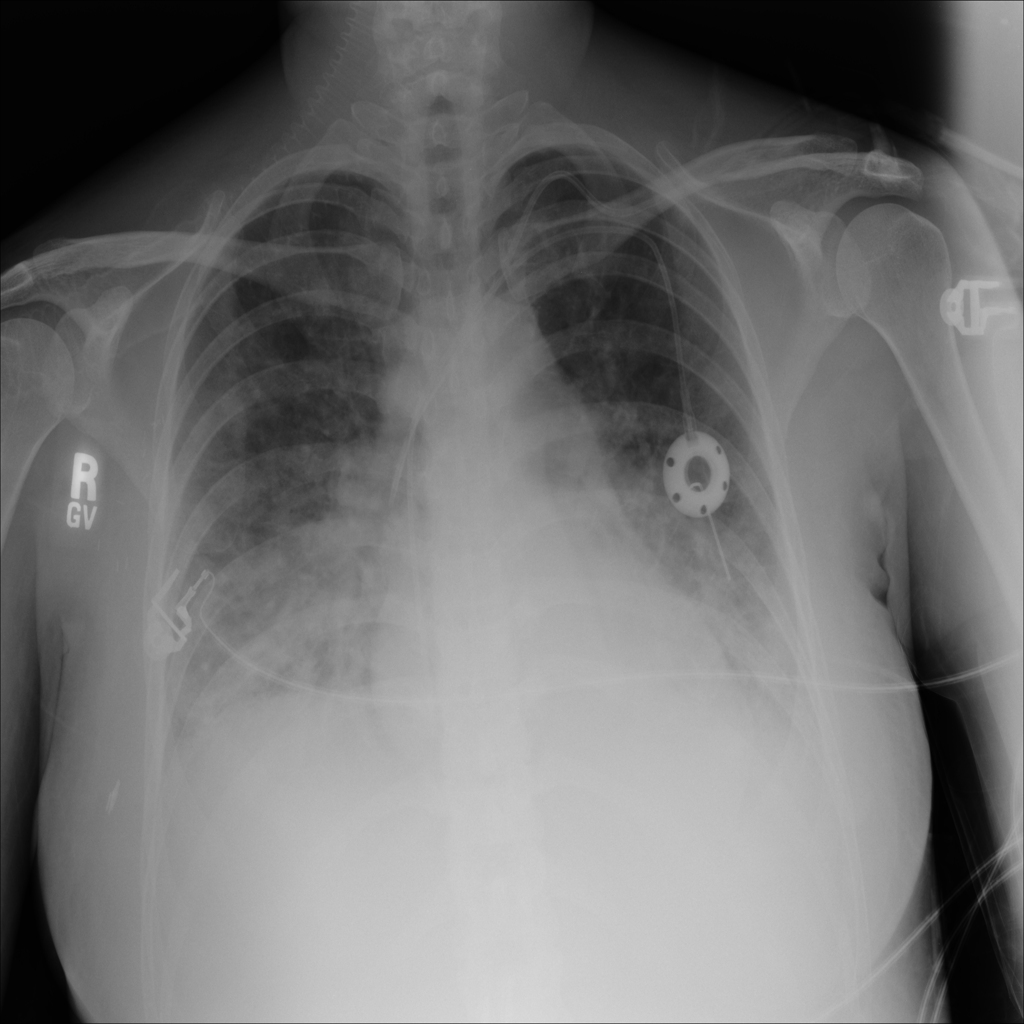

PAT-C0E5 · IMG-015Pneumonia

PAT-C0E5 · IMG-015

AP